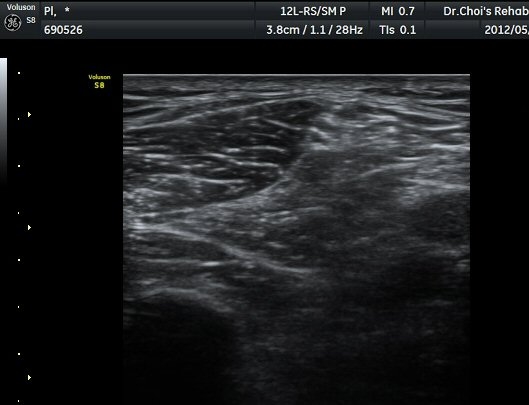

ŽÃËÁö¸¦ Á¶±Ý ´õ ¾Æ·¡·Î À̵¿ÇÏ´Ï »ÀÀÇ µÎ²²°¡ °¨¼ÒÇÏ´Â °ÍÀ» º¸°í ºñ°ñÀÇ ¸ñ ºÎÀ§¸¦ °üÂûÇϰí ÀÖÀ½À» ¾Ë ¼ö ÀÖ°í ÃѺñ°ñ ½Å°æÀº ºñ°ñ ¸ñ Ç¥Ãþ¿¡¼­ °üÂûµÈ´Ù(±×¸² 5).